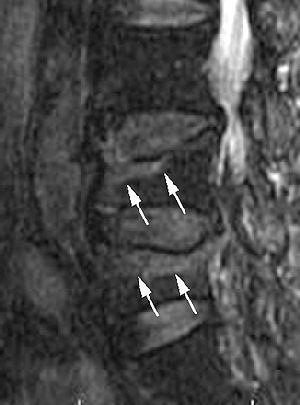

The MR images were reviewed by Tanigawa's co-authors, Dr. Koshi Ikeda, Ph.D, and Dr. Naoto Omura, both neuroradiologists. Regions that exhibited signal intensity lower than that of fatty bone marrow on T1-weighted images and higher than fatty bone marrow on T2-weighted images were indicative of edema, according to the study's classification system.

- Group 1, type 1: bone marrow edema present in 50% or more of the vertebral body

- Group 2, type 2: bone marrow edema present in less than 50% of the vertebral body

| Sagittal T1-weighted (above) and fat-suppressed T2-weighted (below) MR images of osteoporotic compression fracture of L4 and L5 vertebral bodies with considerable bone marrow edema pattern in a 74-year-old woman. Regions of low signal intensity (arrows) are present in the anterosuperior portion of L4 and L5 in image above and occupy less than 50% of the vertebrae. Regions of high signal intensity (arrows) are seen in the anterosuperior portion of L4 and L5 in image below. The high signal intensity regions occupied less than 50% of the vertebrae (group 2). |